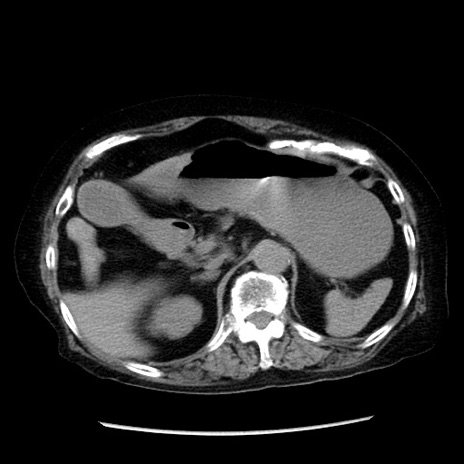

症例14(横断像)

【症例】 90歳代女性

【主訴】 腹痛・嘔吐

【現病歴】今朝から左側腹部痛を認めた。 経過観察していたが、嘔吐を認めたため来院。

【既往歴】 子宮癌術後

【身体所見】 意識清明、BP 127/54mmHg、P 98bpm Sp02 95%(RA)、BT 35.8°C、腹部平坦・軟腸ぜん動音聴取良好、右下腹部圧痛(+) 反跳痛なし

【データ】WBC 9800、CRP 0.46